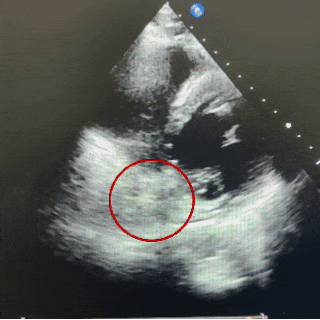

主动脉短轴切面

四腔心切面

超声下可见封堵器稳定夹持在房间隔两侧,呈“Y”字形牢牢抱住主动脉,盘面贴合,形态良好。

在应对此类主动脉侧无残端且合并软缘的房间隔缺损时,若封堵器型号过小,可能无法获得稳定锚定,易发生封堵不全或移位风险;而选择偏大的封堵器虽能增加接触面积与摩擦力,但传统金属封堵器存在磨损主动脉、影响瓣膜功能甚至引起主动脉壁穿孔等风险。相较之下,MemoSorb可降解房间隔缺损封堵器凭借其专利降落伞成型锁定设计,相比金属封堵器有效提高1.8倍封堵器夹持力,即使面对缺损较大、边缘不良的情况,锁定后也可牢固夹持缺损。其采用的生物高分子材料,生物相容性更好,不易磨损主动脉根部。术后超声多切面显示封堵器形态良好,短轴切面下封堵器呈“Y”字形抱主动脉,盘面贴壁紧密,未见残余分流,术后患者自述头痛症状显著缓解。